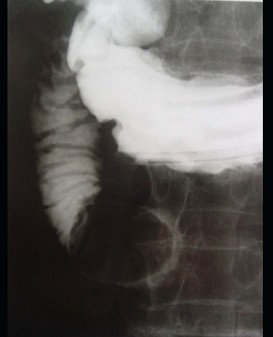

女 ,80岁 ,右上腹疼痛反复发作 6个月,加重 2天 ,曾有胆囊炎及胆结石病史,影像检查如图,应诊断为 ( ) WXJ-04341.jpg WXJ-04342.jpg WXJ-04343.jpg

• A.十二指肠巨大胆结石(胆囊十二指肠瘘)